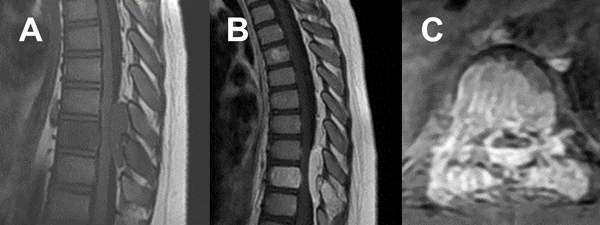

Paciente masculino de 11 años hospitalizado por dorsalgia, paraparesia progresiva severa y retención urinaria. La tomografía computada (TC) y las imágenes de resonancia magnética (RM) revelaron una lesión a nivel D8 y D9, (Figuras 1 y 2). Debido a la rápida progresión de los síntomas se indicó tratamiento quirúrgico al quinto día de internación.

Figura 2. RM prequirúrgica. A) Secuencia T1 sagital. B) Secuencia T1 sagital con gadolinio. C) Secuencia T1 axial con gadolinio.

Las imágenes de resonancia magnética (RM) pueden anticipar las características del hemangioma a tratar. Habitualmente, los HV son hiperintensos tanto en T1 como en T2. Sin embargo, cuando son activos, agresivos o invasivos (Enneking III), suelen ser isointensos en T1 e hiperintensos en T2 (ver Figura 2). Según Daniel Eichberg, la embolización tumoral puede realizarse de forma prequirúrgica para facilitar la cirugía. Algunos autores informan que este procedimiento puede ser un tratamiento único con respuestas curativas, sin embargo, otros describen una respuesta meramente temporal o nula en HV grados III sin cirugía postembolización ni radioterapia.3 Finalmente, la radioterapia, como afirma Keaton Piper, puede usarse como monoterapia para el dolor o como complemento de la cirugía, demostrando una disminución de la recidiva a los 2 años en resecciones subtotales de un 7 a un 30%.5